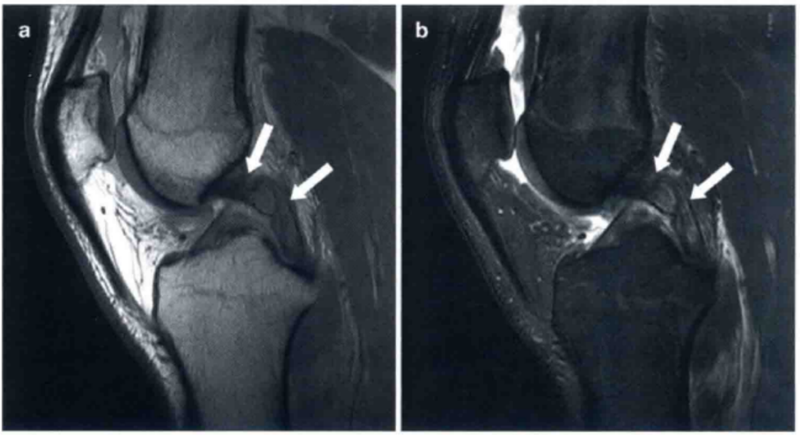

图1 a和b分别显示的是在T2图像中矢状位和轴位正常的ACL。

a显示绷紧,可见明显的ACL低信号(白色箭头)。在a中也显示正常的胫骨附着点(圆形标记)。b显示在水平面上正常的股骨附着点